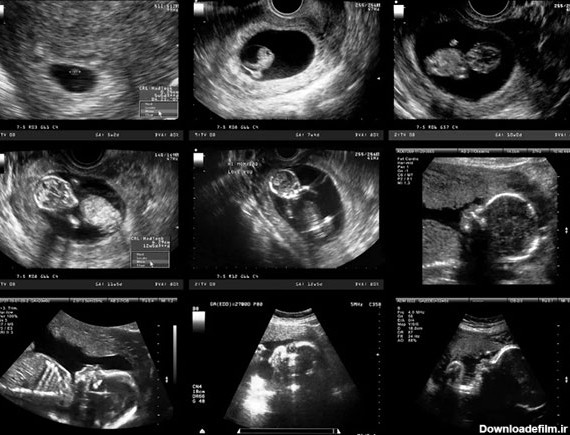

تصاویر سونوگرافی سه ماهه اول جنین – هفته هفتم تا دوازدهم این محیط برای رشد و نمو همچنین حرکت جنین است مایع آمنیوتیک جنین را از هر گونه فشار خارجی روی شکم محافظت می...

روند رشد جنین در سه ماهه اول بارداری و بررسی مراحل رشد جنین در هفته اول تا هفته دوازدهم در بهترین سونوگرافی بارداری در تهران و تهرانپارس